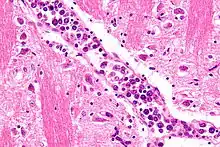

| Micrograph showing an intravascular large B-cell lymphoma in a blood vessel of the brain. H&E stain. | |

The diagnosis of IVBCL is heavily dependent upon obtaining biopsy specimens from involved tissues, particularly the skin but in cases without skin lesions, other apparently involved tissues. Microscopic examination of these tissues typically shows medium-sized to large-sized lymphocytes located within small- to medium-sized blood vessels of the skin, lung, and other tissues or the sinusoids of the liver, bone marrow, and spleen. On occasion, these malignant cells have the appearance of Reed-Sternberg cells. The lesions should show no or very little extension outside of blood vessels. As determined by immunohistochemistry analyses, the intravascular malignant lymphocytes express typical B-cell proteins, particularly CD20, which is found in almost all cases, CD79a and Pax5, which are found in most cases,[5] and MUM1 and Bcl-2, which are found in 95% and 91% of cases, respectively.[2] These B-cells are usually (80% of cases) non-germinal center B-cells (see Pathophysiology section) and may express one or more of the gene, chromosome, and gene expression abnormalities described in the above Pathophysiology section. Since the classical variant can present with a wide range of clinical signs, symptoms, and organ involvements, its presence may not be apparent, particularly in cases that do not exhibit clinically apparent skin lesions. Accordingly, random skin biopsies have been used to obtain evidence of IVL in cases that have signs and/or symptoms of the disease that are restricted to non-cutaneous sites,[2] even in cases that present with no other finding except unexplained fever.[17] The diagnosis of IVBCL, classical variant is solidified by finding these pathological features in more than one site.[2]